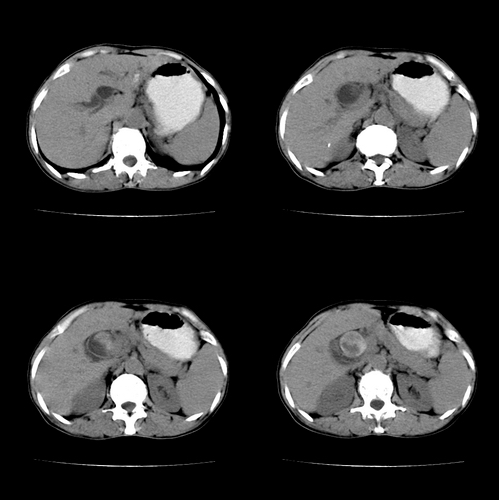

患者 女 60岁,曾多年胆结石及胆管结石,今行ct复查,非常经典.现上传,请讨论.

对不起,第8幅应位于第6幅前.

支持胆总管结石。胆囊增大受压,肝内胆管及胰腺管无明显扩张。很有意思的病例,能有冠、矢状重建图像观察就更好了。

结石这么大,肝内胆管扩张不明显,胆囊扩张明显。能否考虑结石位于胆囊管内并外压总肝管?